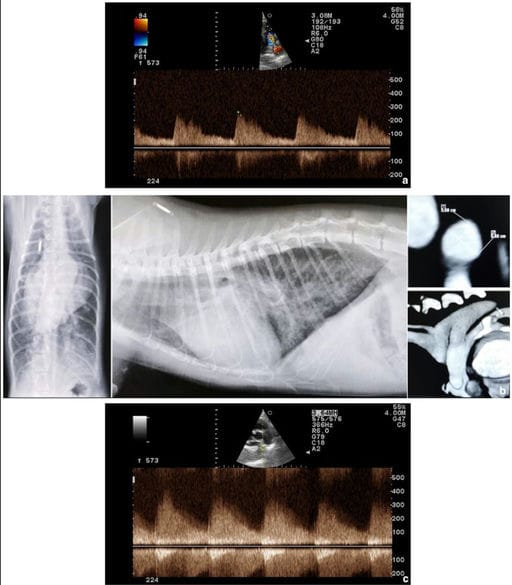

(a) Right parasternal short-axis view of the heart base at the level of pulmonary arteries optimised for spectral Doppler interrogation of ductal flow, demonstrating continuous left-to-right shunting with a reduced velocity through the patent ductus arteriosus (PDA) (unrestrictive pulsatile flow) before surgery in case 1. (b) Thoracic radiography (right lateral and dorsoventral view) and CT showing severe cardiomegaly, increased pulmonary vascular markings, diffuse interstitial-alveolar pattern and a large tubular PDA without any constrictions at its ends, respectively. Notice the prominent main pulmonary artery and leftward bulge of the aorta in thoracic dorsoventral view (case 1). (c) Right parasternal short-axis view of the heart base at the level of pulmonary arteries optimised for spectral Doppler interrogation of pulmonary artery/ductal flow after surgical closure of the PDA in case 1, demonstrating predominantly continuous flow below the baseline throughout the diastole, resembling a ‘sawtooth’ flow pattern suspicious of pulmonary artery branch stenosis and reversed PDA